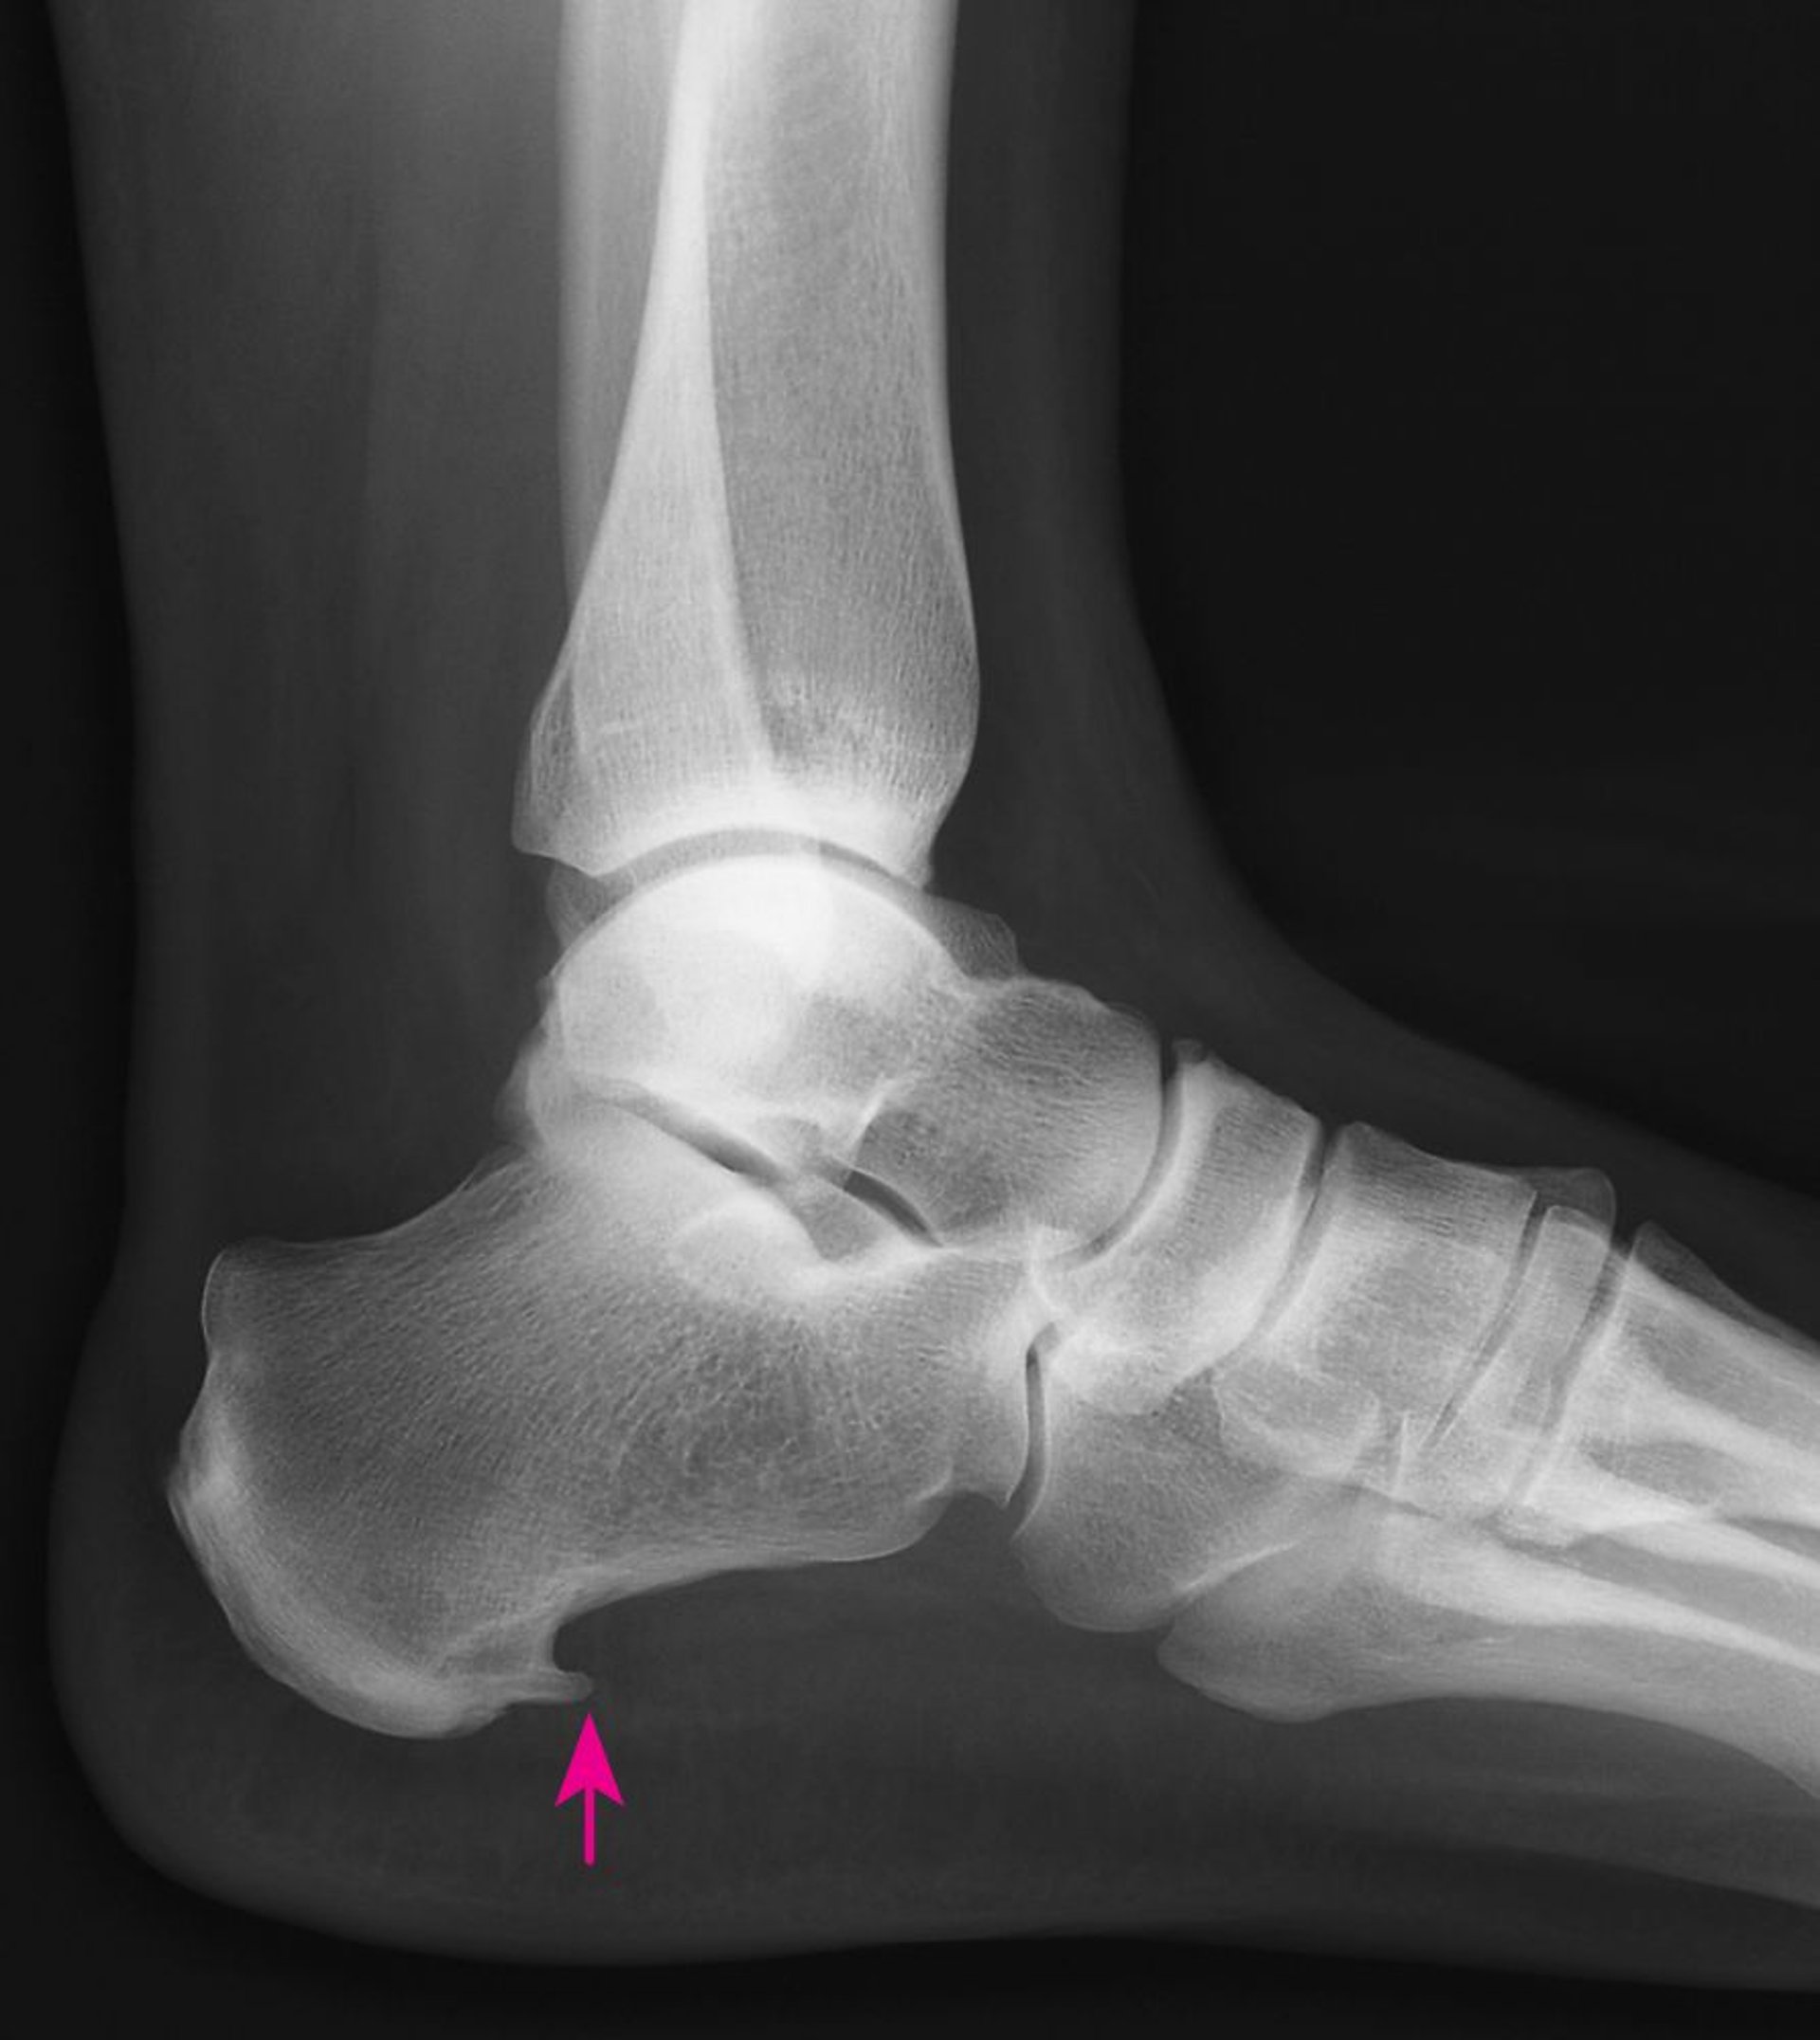

踵骨棘

このX線写真には、踵骨棘(しょうこつきょく)と呼ばれる、かかとの骨の下側に余分なとがった骨が増殖したものが写っています。